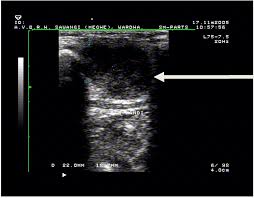

An ultrasound may be used to check for certain cancers in various different ways. What an ultrasound can detect? 31 533 просмотра • 28 сент. Cysts or abnormal growths in the liver, spleen, or pancreas. Brook's personal experiences as a patient with throat they are also used to detect cancer and follow up its progression and response to therapy. Some genetic disorders, such as fanconi anemia, can increase the risk of developing precancerous lesions and cancers early in life (30). Sometimes the cancer cells can spread into the nearby lymph nodes. Ultrasound can detect abnormalities indicating cancer in breast, liver, etc., but a definite diagnosis requires further tests like ct or mri scan. However, ultrasound does not produce images with the same level of clarity or detail as a ct or mri scan, nor can it confirm a cancer diagnosis on its own. A scanner then detects this substance to produce images. Ultrasound image of a neck mass. For head and neck cancers, immunotherapy medications may act on a specific protein in immune. An ultrasound of the neck uses high frequency sound waves to create a live image from inside of a patient's body.